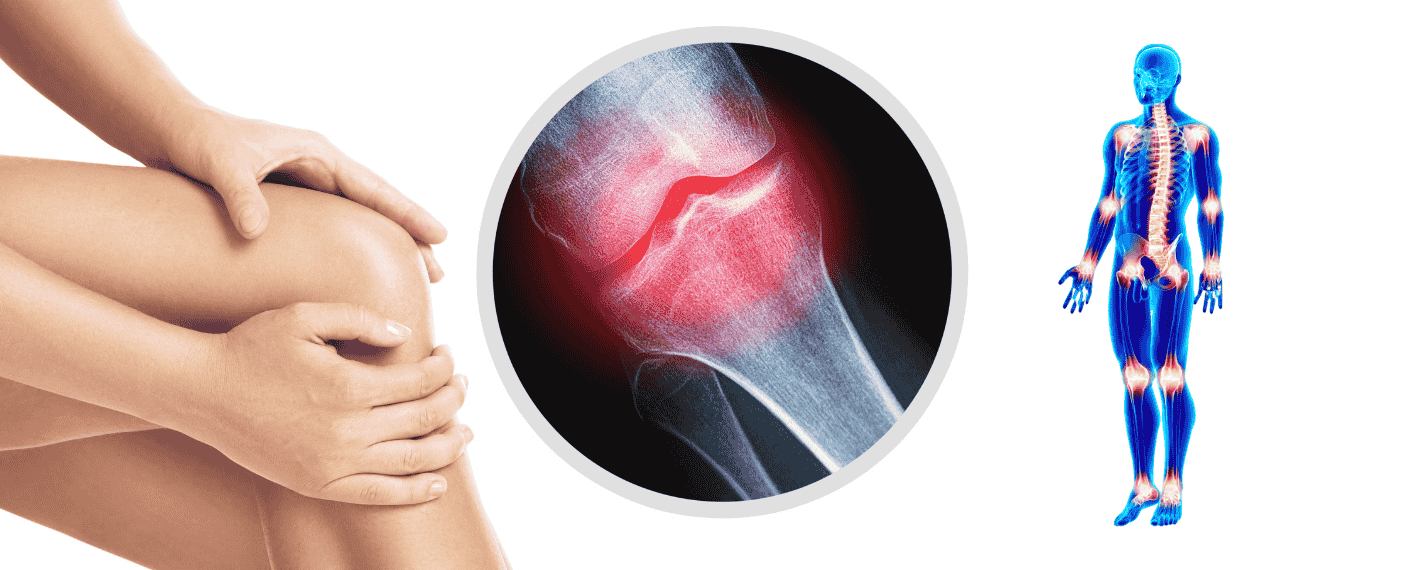

Joint & Bone Care

Joint and bone health is essential for maintaining mobility, independence, and quality of life, especially as we age. At DRS Homeo, Dr. Shwetha Badam offers effective homeopathic treatments for conditions such as arthritis, osteoporosis, back pain, sciatica, and joint stiffness. Her approach focuses on reducing inflammation, relieving pain, and improving joint flexibility without the side effects of long-term painkiller use or invasive procedures.

With over 12 years of experience in holistic healthcare, Dr. Shwetha combines personalized homeopathic remedies with lifestyle counseling and nutritional support to strengthen bones and support joint function. Whether you're recovering from an injury or managing a chronic condition, her integrative care helps restore balance, ease discomfort, and promote long-term musculoskeletal wellness. At DRS Homeo, patients receive compassionate, result-driven care that supports both mobility and overall well-being.